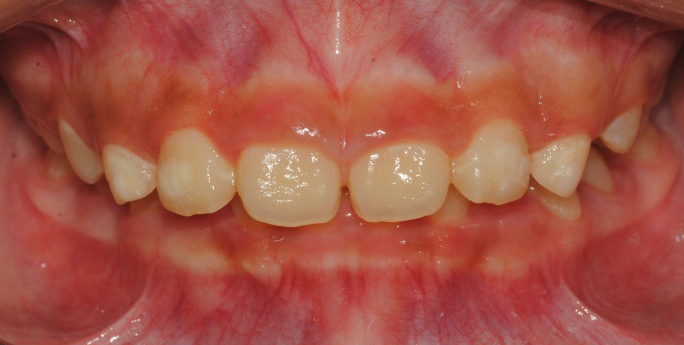

À§ ȯÀÚ´Â À´Ï°¡ ¾Æ·§´Ï¸¦ ³Ê¹« µ¤¾î¿ä(°ú°³±³ÇÕ) ¸¦ ÁÖ¼Ò·Î ³»¿øÇÑ ÃʵîÇлýÀ̾ú½À´Ï´Ù. ÅμºÀå ¾ÇÁ¤ÇüÀåÄ¡ »ç¿ëÈÄ È£ÈíÀÌ °³¼± µÇ¾úÀ¸¸ç Ä¡·áÀü¿¡ ºñÇØ ۰¡ 10cmÁ¤µµ ±Þ¼Ó ¼ºÀåÇÏ¿´½À´Ï´Ù.